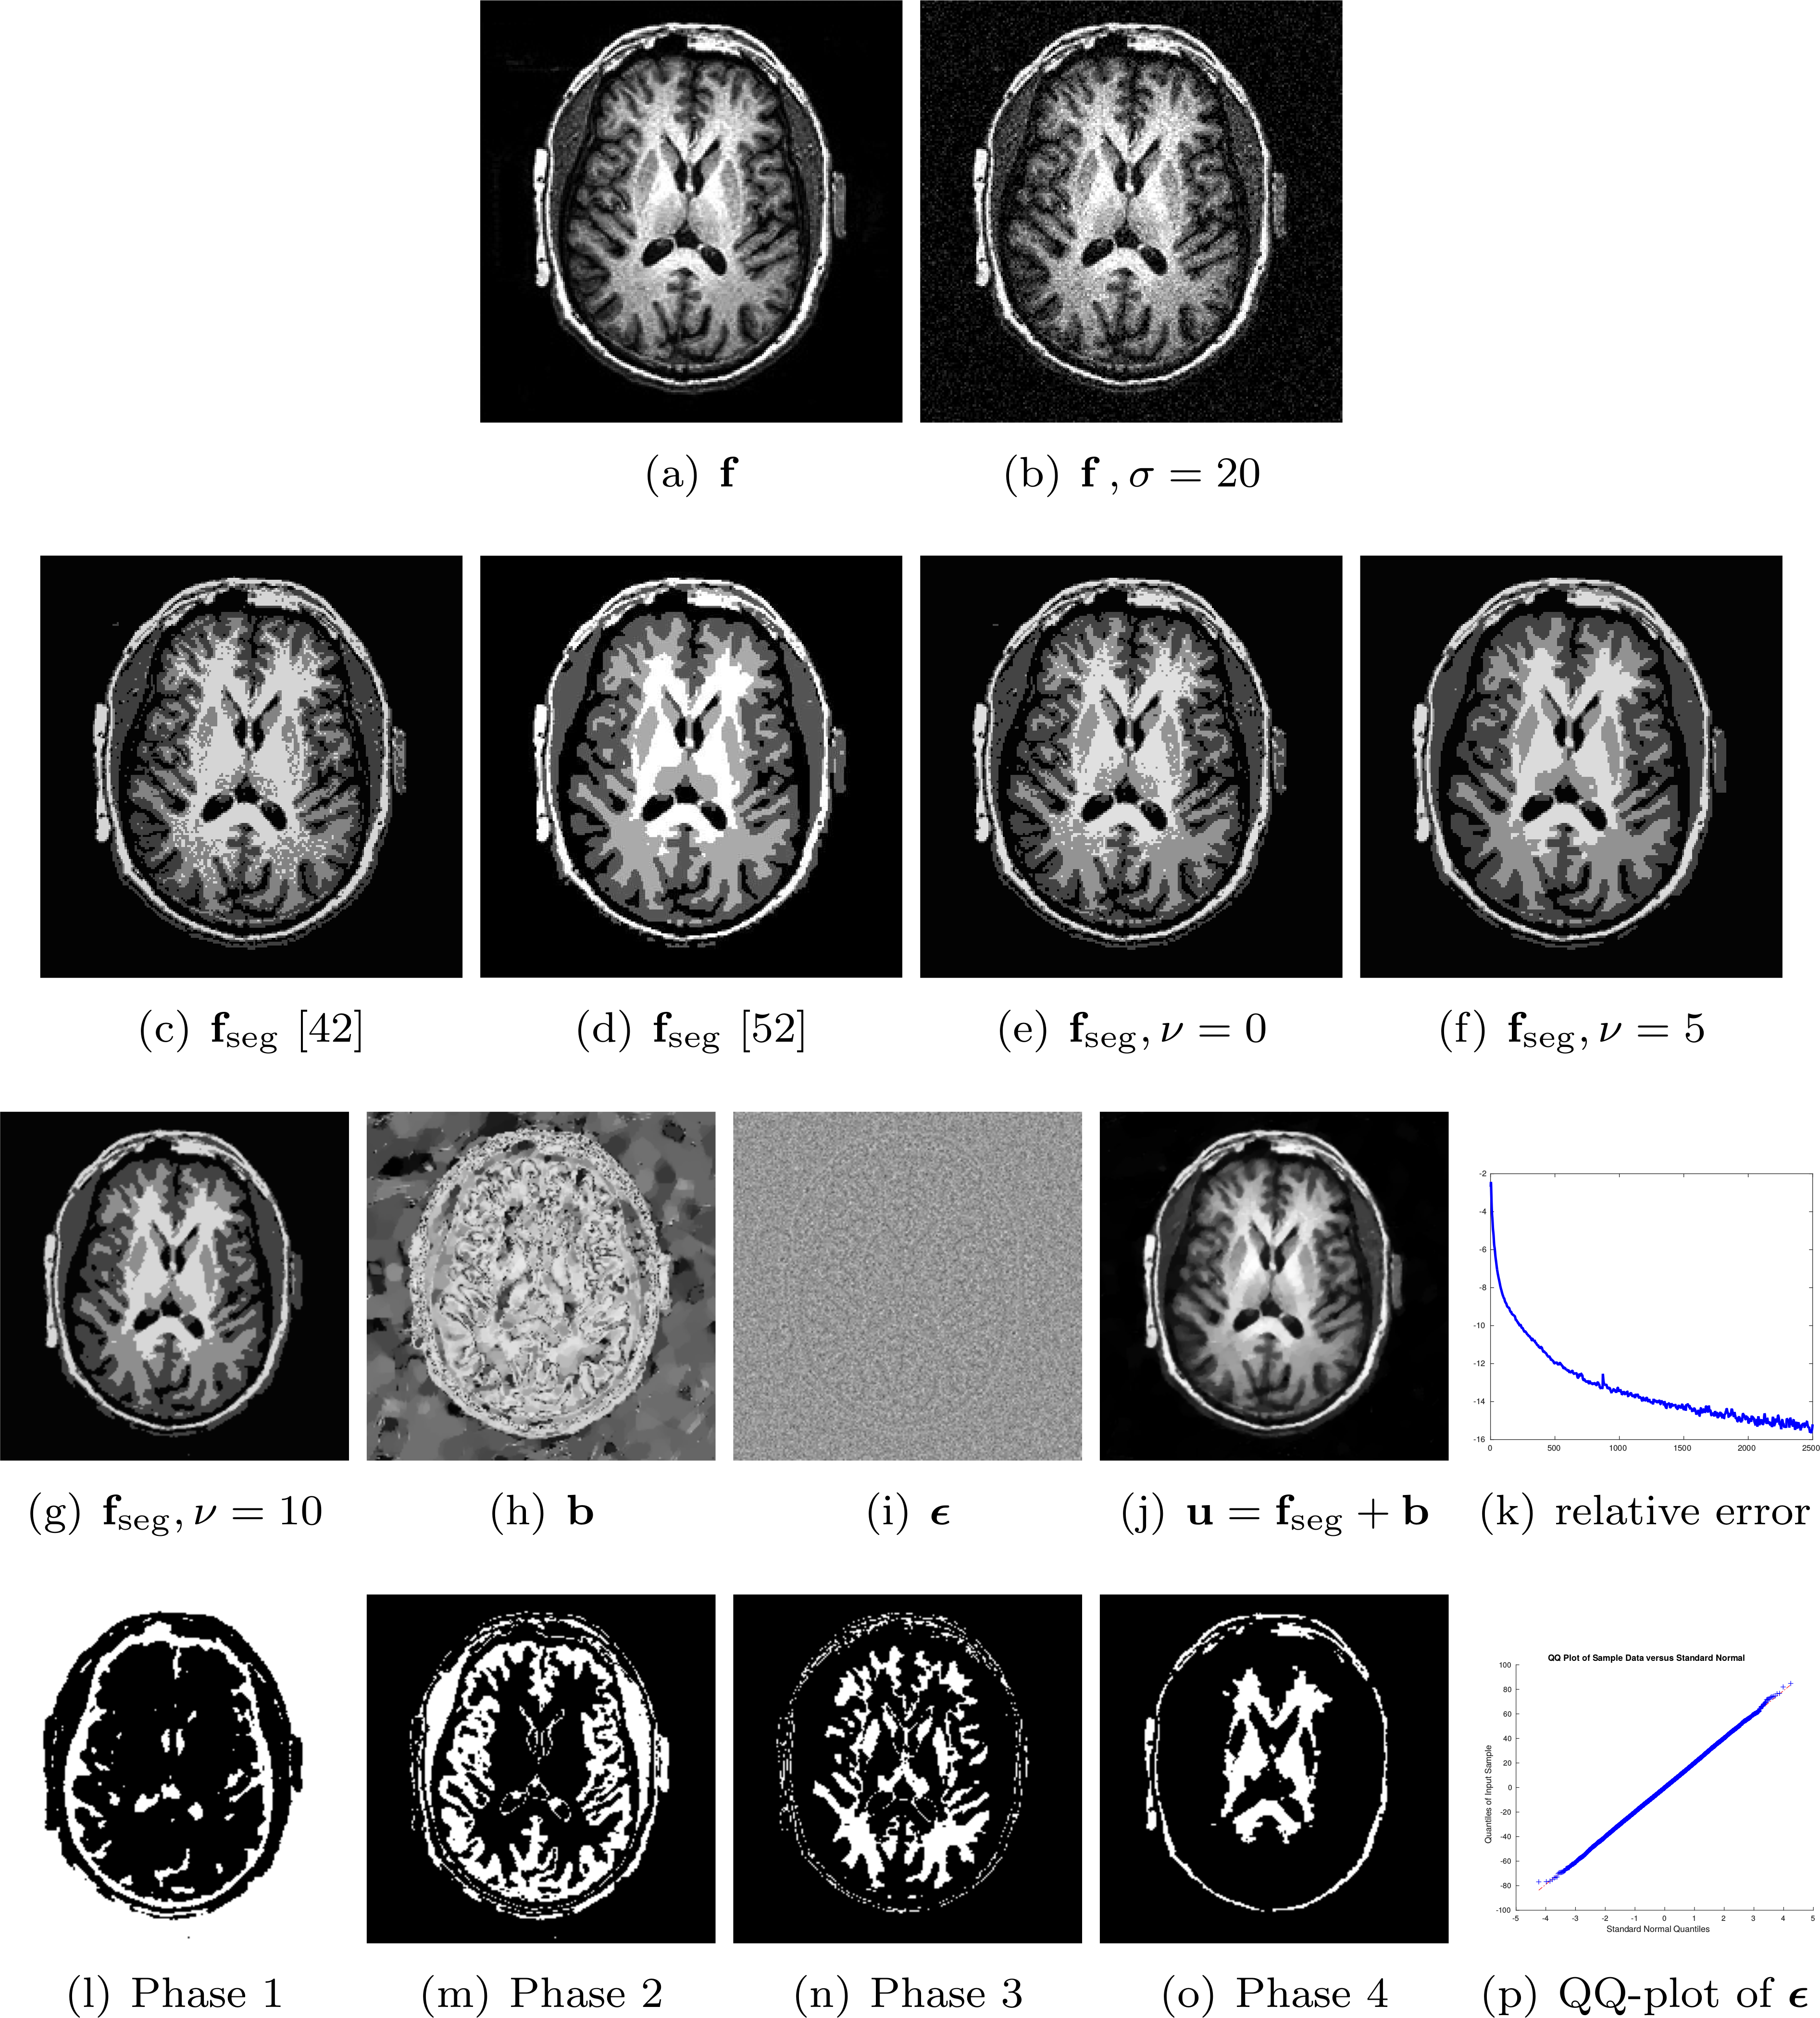

This solution is summarized in Algorithm 1. Figures 5 and 6 depict the segmented results without noise and with independent Gaussian noise, respectively. In both cases, our proposed method provides good segmented results, though some large-scale texture (e.g. the books shown in the upper left-hand corner) still remains in the piecewise constant images; see Figures 5 (f) and 6 (f). This is likely due to the minimizer obtained by the primal-dual method with Chambolle’s projection [34] and since there is no shrinkage to produce sparse signals in some transform domains. Similar to (2.1), one can use the technique in [42] to obtain a binary setting of 𝐩𝐩{\mathbf{p}}. As in [7, 55], the convergence of the algorithm is defined by a relative error on the log scale

Refer to caption

Figure 5: The original image 𝐟𝐟{\mathbf{f}} (a) is decomposed into a bias field 𝐛𝐛{\mathbf{b}} (e), a piecewise constant image 𝐟segsubscript𝐟seg{\mathbf{f}}_{\text{seg}} (f), small scale objects (residual) ϵbold-italic-ϵ{\boldsymbol{\epsilon}} (g), and sparse texture 𝐯𝐯{\mathbf{v}} (h) with binarized verion 𝐯binsubscript𝐯bin{\mathbf{v}}_{\text{bin}} in (l). A piecewise smooth image 𝐮𝐮{\mathbf{u}} (b) is obtained by a summation of 𝐛𝐛{\mathbf{b}} (e) and 𝐟segsubscript𝐟seg{\mathbf{f}}_{\text{seg}} (f). Subfigure (c) shows segmented contours superimposed on 𝐮𝐮{\mathbf{u}}. The relative error of 𝐮𝐮{\mathbf{u}} is shown in (d). The indicator functions for phases 1, 2, and 3 are shown in Subfigures i, j, and k, respectively. The parameters are ν=10,N=3,L=S=M=2,τ=0.1,ξ=0.001,α=μ1=μ2=μ3=0.1,cμ1=0.14,μ4=0.01,β=0.04,#iteration=10000formulae-sequenceformulae-sequence𝜈10formulae-sequence𝑁3𝐿𝑆𝑀2formulae-sequence𝜏0.1formulae-sequence𝜉0.001𝛼subscript𝜇1subscript𝜇2subscript𝜇30.1formulae-sequencesubscript𝑐subscript𝜇10.14formulae-sequencesubscript𝜇40.01formulae-sequence𝛽0.04#iteration10000\nu=10,N=3,L=S=M=2,\tau=0.1,\xi=0.001,\alpha=\mu_{1}=\mu_{2}=\mu_{3}=0.1,c_{\mu_{1}}=0.14,\mu_{4}=0.01,\beta=0.04,\#\text{iteration}=10000. The mean square error of the original image 𝐟𝐟{\mathbf{f}} and a reconstructed image 𝐟re=𝐛+𝐟seg+𝐯+ϵsubscript𝐟re𝐛subscript𝐟seg𝐯bold-italic-ϵ{\mathbf{f}}_{\text{re}}={\mathbf{b}}+{\mathbf{f}}_{\text{seg}}+{\mathbf{v}}+{\boldsymbol{\epsilon}} is MSE=9.02×105MSE9.02superscript105\text{MSE}=9.02\times 10^{-5}.

Figure 6: Original image 𝐟𝐟{\mathbf{f}} with added i.i.d. noise from 𝒩(0,202)𝒩0superscript202\mathcal{N}(0\,,20^{2}) is shown in (a). With the addition of noise, we choose ν=16𝜈16\nu=16 with the remaining parameters set similar to those in Figure 5. The QQplot in (c) for noise ϵbold-italic-ϵ{\boldsymbol{\epsilon}} in (g) shows that ν=16𝜈16\nu=16 can separate most of the noise and some texture information. The MSE is 7.47×1057.47superscript1057.47\times 10^{-5}. Note that increasing L𝐿L will not make 𝐮𝐮{\mathbf{u}} (b) smoother due to the lack of a sparsity constraint in Chambolle’s projection. The algorithm still performs well with sparse texture 𝐯𝐯{\mathbf{v}} as illustrated in (l).